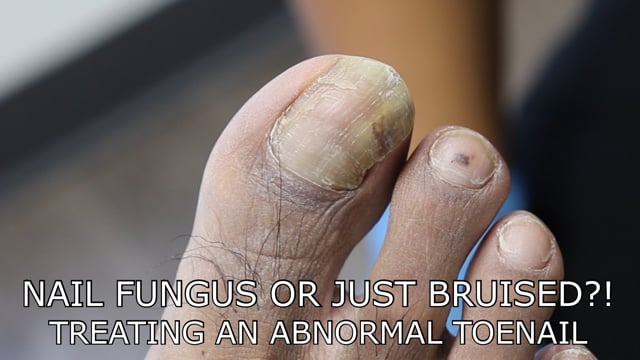

Is this toenail fungus or a damaged toenail?!

January 10, 2023

Toenail Care